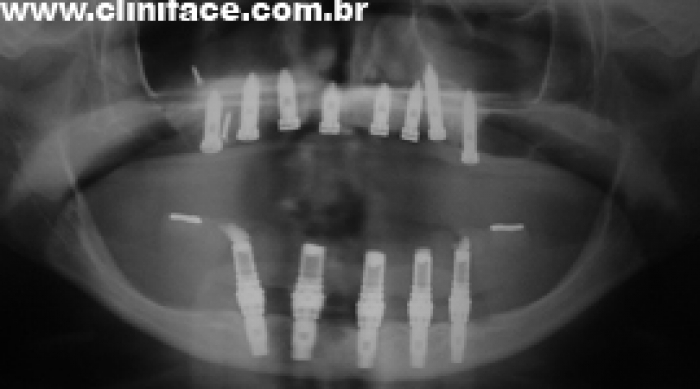

Raio X de controle, realizado em Abril de 2013 - Clínica Cliniface

Raio X de controle, realizado em Abril de 2013